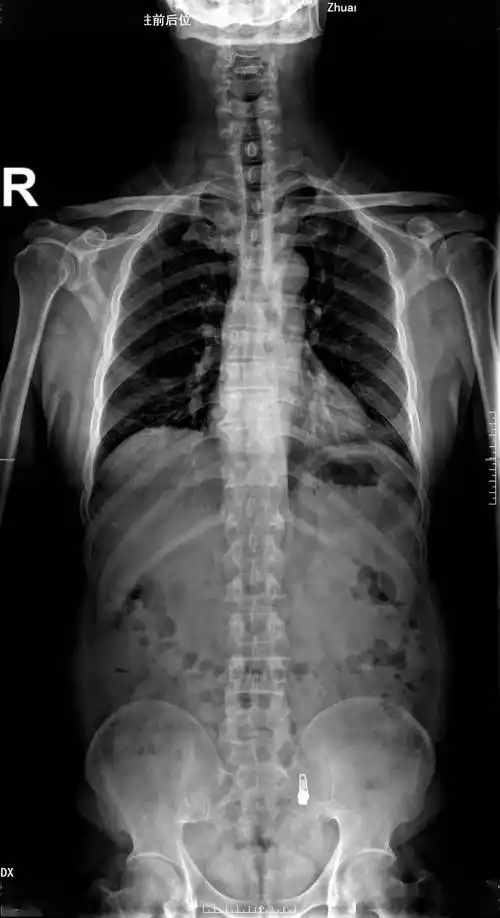

功能强,成像快,辐射小,全县首台大动态平板数字x线机在湖口县人民医院

气胸的x线表现6个病例帮你搞定